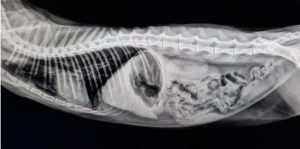

Eskiden teşhis edilemeyen bazı hastalıkların, modern tanı ekipmanlarının kullanımıyla artık kolaylıkla tespit edilebildiğini aktaran Civelek, ”Veteriner hekimlik için kan analizleri, röntgen, endoskopi, ultrasonografi günümüzde rutin uygulamalardır, hemen her klinikte yapılabilmektedir. Hatta ülkemizde birçok merkezde artık tanıda bilgisayarlı tomografiden ve hatta MRI’dan yararlanılıyor. Daha önce nadir gözlendiği düşünülen bazı hastalıklar ise günümüzde bu tip ileri ekipmanlarının kullanımıyla artık büyük doğrulukla tanı alıyor.” dedi.

Civelek, bu vakaya, kendisinin lisansüstü danışmanlığını yürüttüğü veteriner hekimler Ender Erkoç ve Cankan Alpay’ın kliniklerinde, tekir ırkı erkek bir kedide rutin kalp ultrasonografisi (ekokardiyografi) sırasında rastlandığını ifade ederek, şu bilgileri verdi:

”Kesin tanı için bizden destek istediler. Görüntüleri incelediğimizde bunun nadir gözlenen bir tümör olabileceğini gördük. Olayı tanımladık ve bilim dünyasına kazandırdık. Kalp hastalıklarına her yaştaki kedi ve köpeklerde sıklıkla rastlanmaktadır. Kardiyak tümörlere ise kedilerde nadir rastlanır. Bu tümörlerin teşhisi genellikle ekokardiyografik muayene yani kalbin ultrasonografisiyle yapılır. Sunulan vakadaki ‘papillar fibroelastoma’ primer bir kalp tümörüdür ve iyi huylu olarak bilinir. Bununla birlikte, bu tip tümörler tromboemboli (pıhtı atma) riski taşır, felç ya da enfarktüs gibi komplikasyonlara sebebiyet verebilir. Bu tip olgulardaki belirtiler net değildir ve kitlenin boyutu veya yapısıyla bağlantılı olarak değişkenlik gösterebilir.”